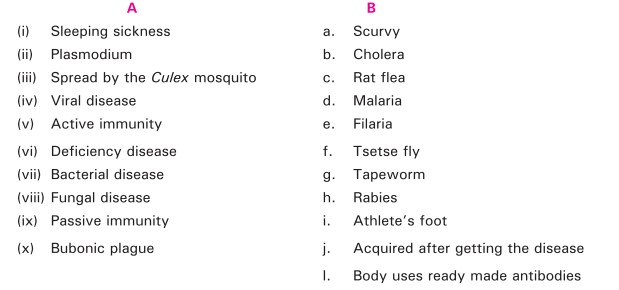

Q-9 Match the item in column A with item in column B.

Q-18 Match the item in column A with item in column B.